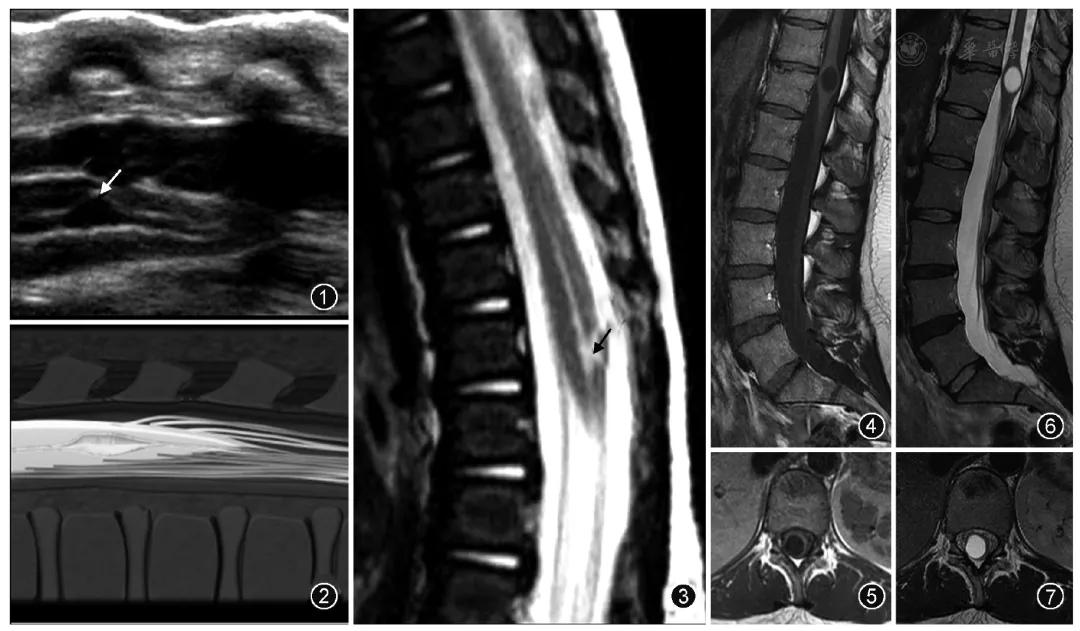

超声是诊断胎儿或新生儿第五脑室的一种常用检查方法。第五脑室在超声矢状切面图上显示为脊髓圆锥区域囊状扩张的低回声区并可与中央管相通,在超声横断切面图上表现为扩张的低回声囊腔且与周围脊髓组织有着较为清楚的分界。

来自杂志图片

MR检查为诊断第五脑室的主要手段。第五脑室在MRI上通常表现为脊髓圆锥内边缘清楚的卵圆形囊腔,形态规则,囊壁光整,且与周围正常的脊髓组织分界清楚,囊内为T1WI低、T2WI高的脑脊液信号,囊内分隔及囊周水肿性改变比较少见,增强扫描后囊壁不强化。第五脑室需要与位于脊髓圆锥的囊性肿瘤如室管膜瘤、星形细胞瘤以及脓肿相鉴别,囊性肿瘤和脓肿的囊壁通常有不同程度的强化。脊髓圆锥的转移瘤很少见,MRI表现通常为肿瘤强化且周围伴有明显水肿。脊髓背侧的严重损伤也可发展为囊性病灶,但目前报道的大多数第五脑室病例并无外伤病史。脊髓内的表皮样囊肿和皮样囊肿由于成分复杂导致MRI表现多变,而第五脑室的MRI表现单一。